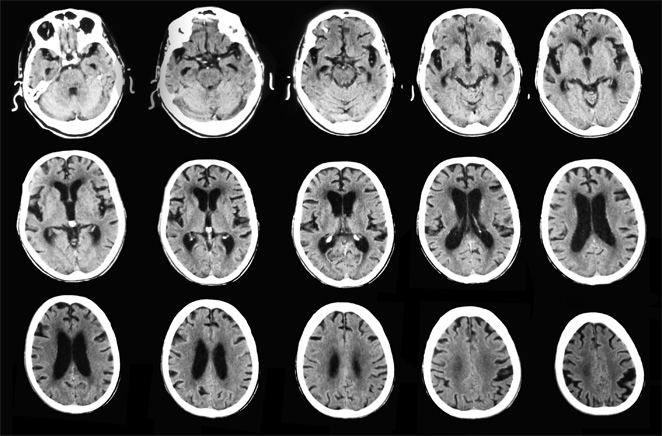

La tomografía computarizada es una prueba de diagnóstico por imágenes que utiliza una combinación de radiografías y tecnología computarizada para obtener imágenes de cortes transversales “rebanadas” del cuerpo, tanto horizontales como verticales. La TC muestra imágenes detalladas de los órganos internos, (huesos, tejidos blandos y vasos sanguíneos).

- Permite identificar hemorragias internas, tumores, lesiones u otros daños.

Debido a las

facilidades en el diagnóstico de imágenes generalmente se realizan exámenes de: Cabeza, Cuello, Columna, Tórax, Pelvis, Abdomen, estructuras Oseas, miembros superiores e inferiores.

![]() |

| Tomografía de Cabeza - Corte Axial |

| Tomografía de Tórax - Corte Axial |